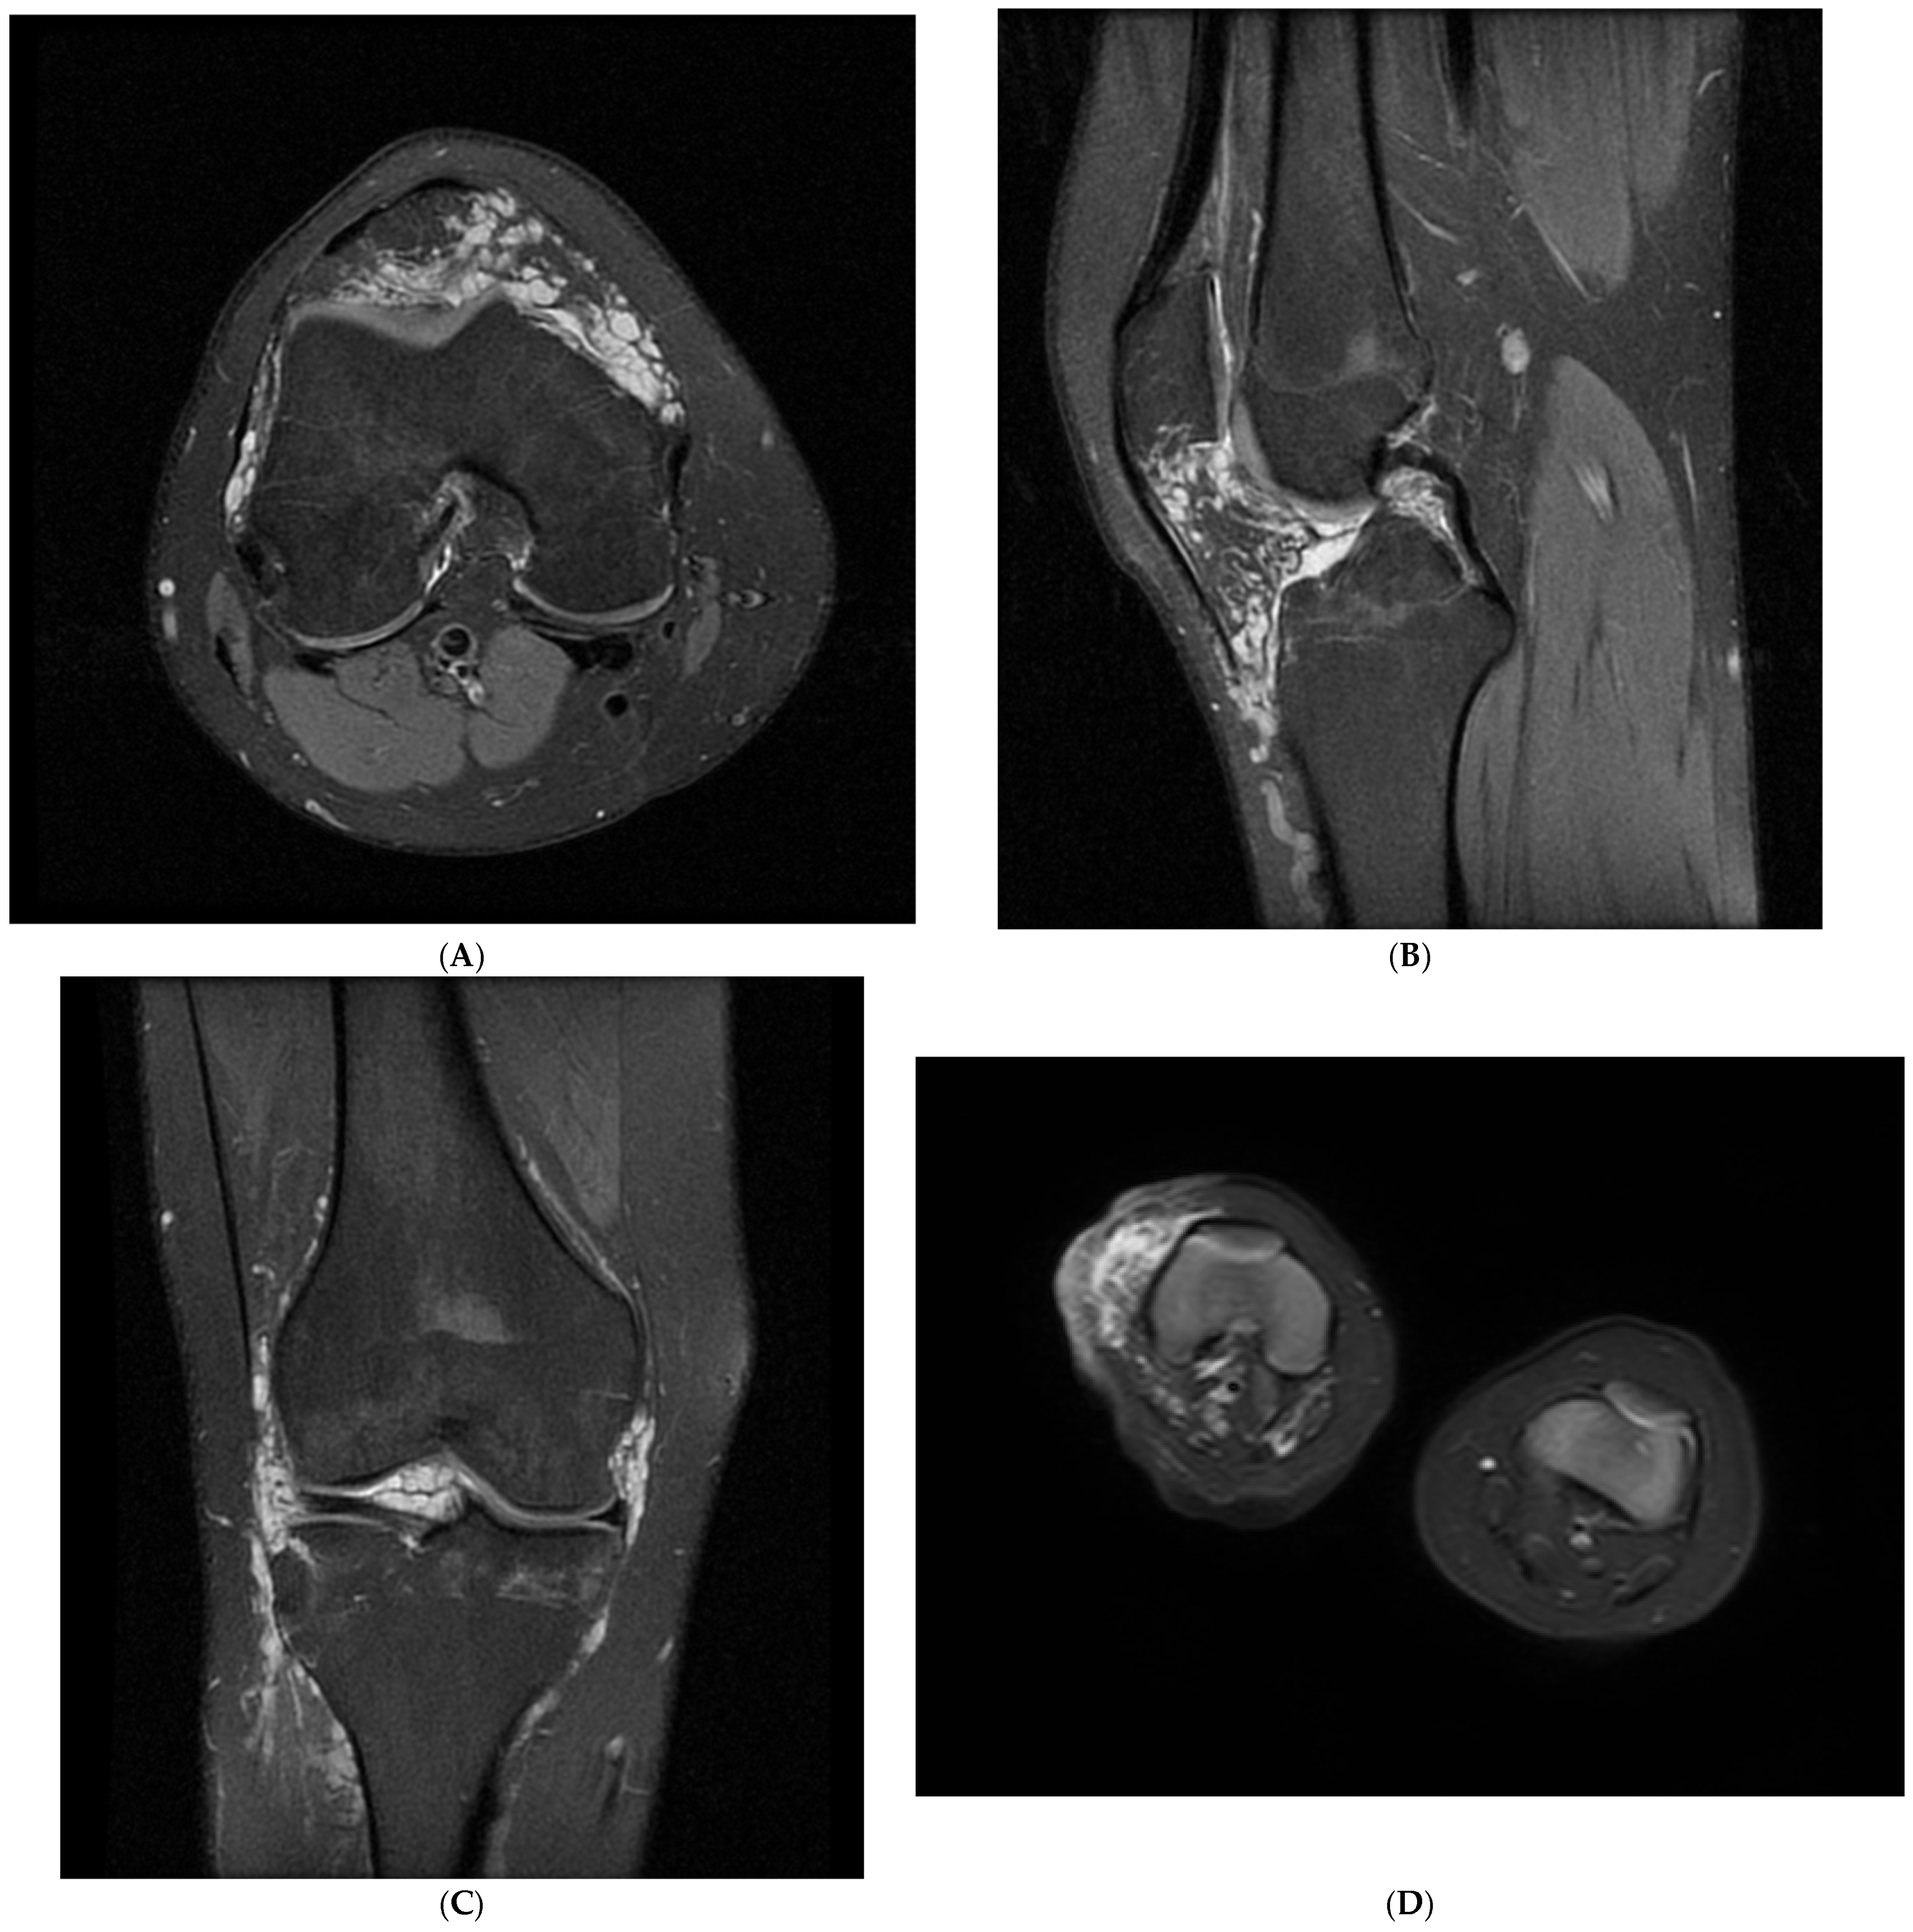

3.3. Radiological Features of VM of the Knee on Contrast-Enhanced MRI

| Patient No. | MRI Sequences Used | Lesion Location | Intra-/Extra-Articular | Extracapsular Structures Involved | Deformation of Affected Limb |

|---|---|---|---|---|---|

| 1 | T1, T2 Fat-Sat, STIR, T2, GRE, T1 Pre-Contrast, T1 Post-Contrast, T1 Post-Contrast Fat-Sat, CE-MRA | Thigh, Hoffa’s fat pad, suprapatellar recess | Both | Subcutaneous tissue, muscles, ligaments | + |

| 2 | T1, T2 Fat-Sat, STIR, PD Fat-Sat, GRE, T1 Pre-Contrast, T1 Post-Contrast Fat-Sat, DWI, CE-MRA | Thigh, crus, Hoffa’s fat pad, suprapatellar recess | Both | Subcutaneous tissue, muscles, ligaments | + |

| 3 | T1, T2, STIR, T2 Fat-Sat, GRE, T1 Pre-Contrast Fat-Sat, T1 Post-Contrast, MRV, CE-MRA | Gluteal region, thigh, Hoffa’s fat pad, suprapatellar recess | Both | Subcutaneous tissue, muscles, ligaments | + |

| 4 | T1, PD, STIR, T2 Fat-Sat, GRE, T1 Pre-Contrast Fat-Sat, T1 Post-Contrast, 3D TOF-MRA, CE-MRA | Thigh, crus, all recesses of knee, Hoffa’s fat pad | Both | Subcutaneous tissue, muscles, ligaments | + |

| 5 | T1, T2, STIR, T2 Fat-Sat, GRE, T1 Pre-Contrast, T1 Post-Contrast, DCE-MRI, CE-MRA | Thigh, Hoffa’s fat pad, suprapatellar recess | Both | Subcutaneous tissue, muscles, ligaments | + |

| 6 | T1, T2, STIR, T2 Fat-Sat, GRE, T1 Pre-Contrast Fat-Sat, T1 Post-Contrast Fat-Sat, MRV, CE-MRA | Gluteal region, thigh, crus, Hoffa’s fat pad, suprapatellar recess | Both | Subcutaneous tissue, muscles, ligaments | + |

| 7 | T1, T2, STIR, T2 Fat-Sat, GRE, T1 Pre-Contrast, T1 Post-Contrast, DTI, CE-MRA | Gluteal region, thigh, crus, foot, Hoffa’s fat pad, suprapatellar recess | Both | Subcutaneous tissue, muscles, ligaments | − |

| 8 | T1, T2, STIR, PD Fat-Sat, GRE, T1 Pre-Contrast, T1 Post-Contrast Fat-Sat, DWI, CE-MRA | Crus, Hoffa’s fat pad, suprapatellar recess | Both | Subcutaneous tissue, muscles, ligaments | + |

| 9 | T1, T2, STIR, T2 Fat-Sat, GRE, T1 Pre-Contrast Fat-Sat, T1 Post-Contrast Fat-Sat, 3D TOF-MRA, CE-MRA | Hoffa’s fat pad, suprapatellar recess | Intra-articular | − | − |